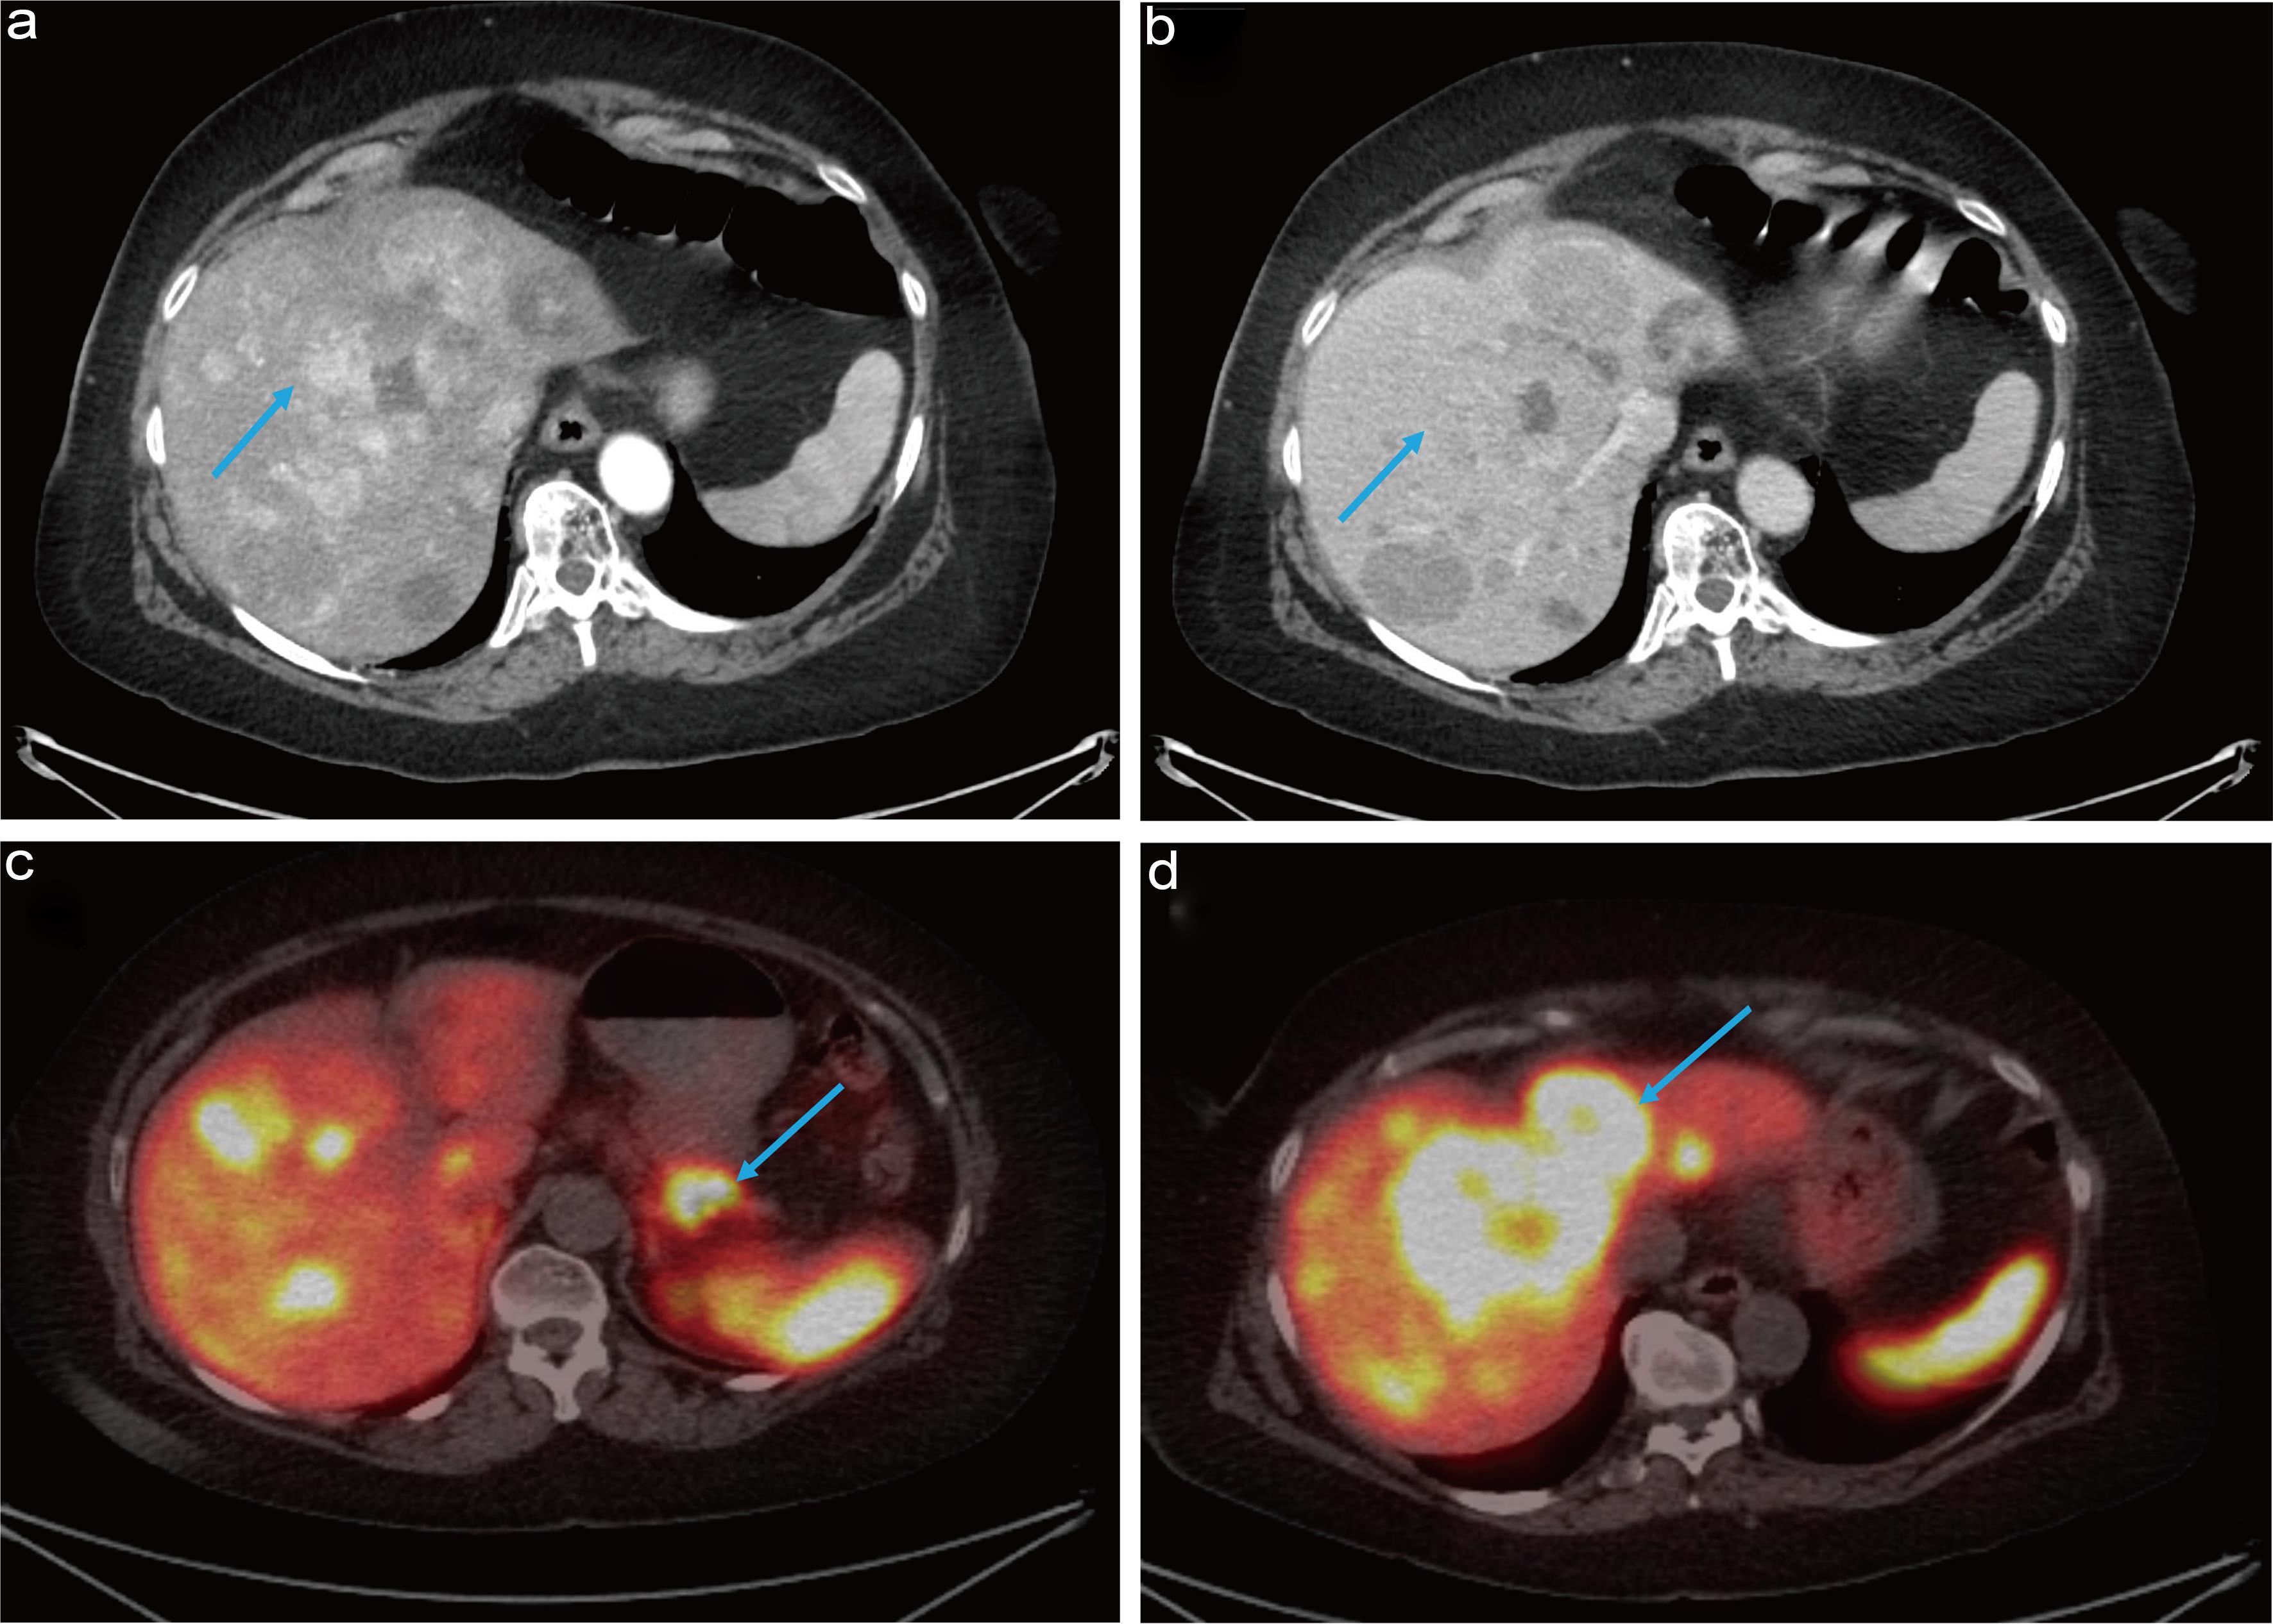

Two months prior to presentation, the patient visited her primary care physician complaining of mid-epigastric pain, reflux, and profuse sweating, symptoms that began shortly after receiving her second dose of the COVID-19 vaccine. An initial ultrasound revealed an 8 × 6.1 × 6.2 cm hyperechoic lesion in the right lobe of the liver, along with four smaller hyperechoic nodules scattered throughout the liver. A follow-up computed tomography (CT) scan of the abdomen and pelvis, performed with and without contrast, identified a noncirrhotic hepatic morphology with several hypodense lesions visible on non-contrast images. These lesions demonstrated arterial phase hyperenhancement exceeding that of the surrounding liver parenchyma, followed by peripheral washout in the portal venous phase (Fig. 1). These imaging features are classic for Liver Imaging Reporting and Data System category 5 lesions, consistent with HCC. Some lesions exhibited smooth, uniform borders suggestive of a capsule, which is typical for HCC. Additionally, the lesions were large (greater than 2 cm), supporting a higher likelihood of malignancy.

Baseline CT imaging (a) non-contrast enhanced, and contrast enhanced- (b) arterial phase demonstrating hyperenhancement, (c) and (d) portal venous phase demonstrating washout.

Fig. 1  Baseline CT imaging (a) non-contrast enhanced, and contrast enhanced- (b) arterial phase demonstrating hyperenhancement, (c) and (d) portal venous phase demonstrating washout.

CT, computed tomography.